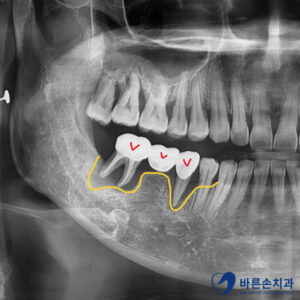

우측 아래 임플란트 2개(노란 화살표)가

임플란트 주위염으로 인해

치조골이 내려가 있습니다.